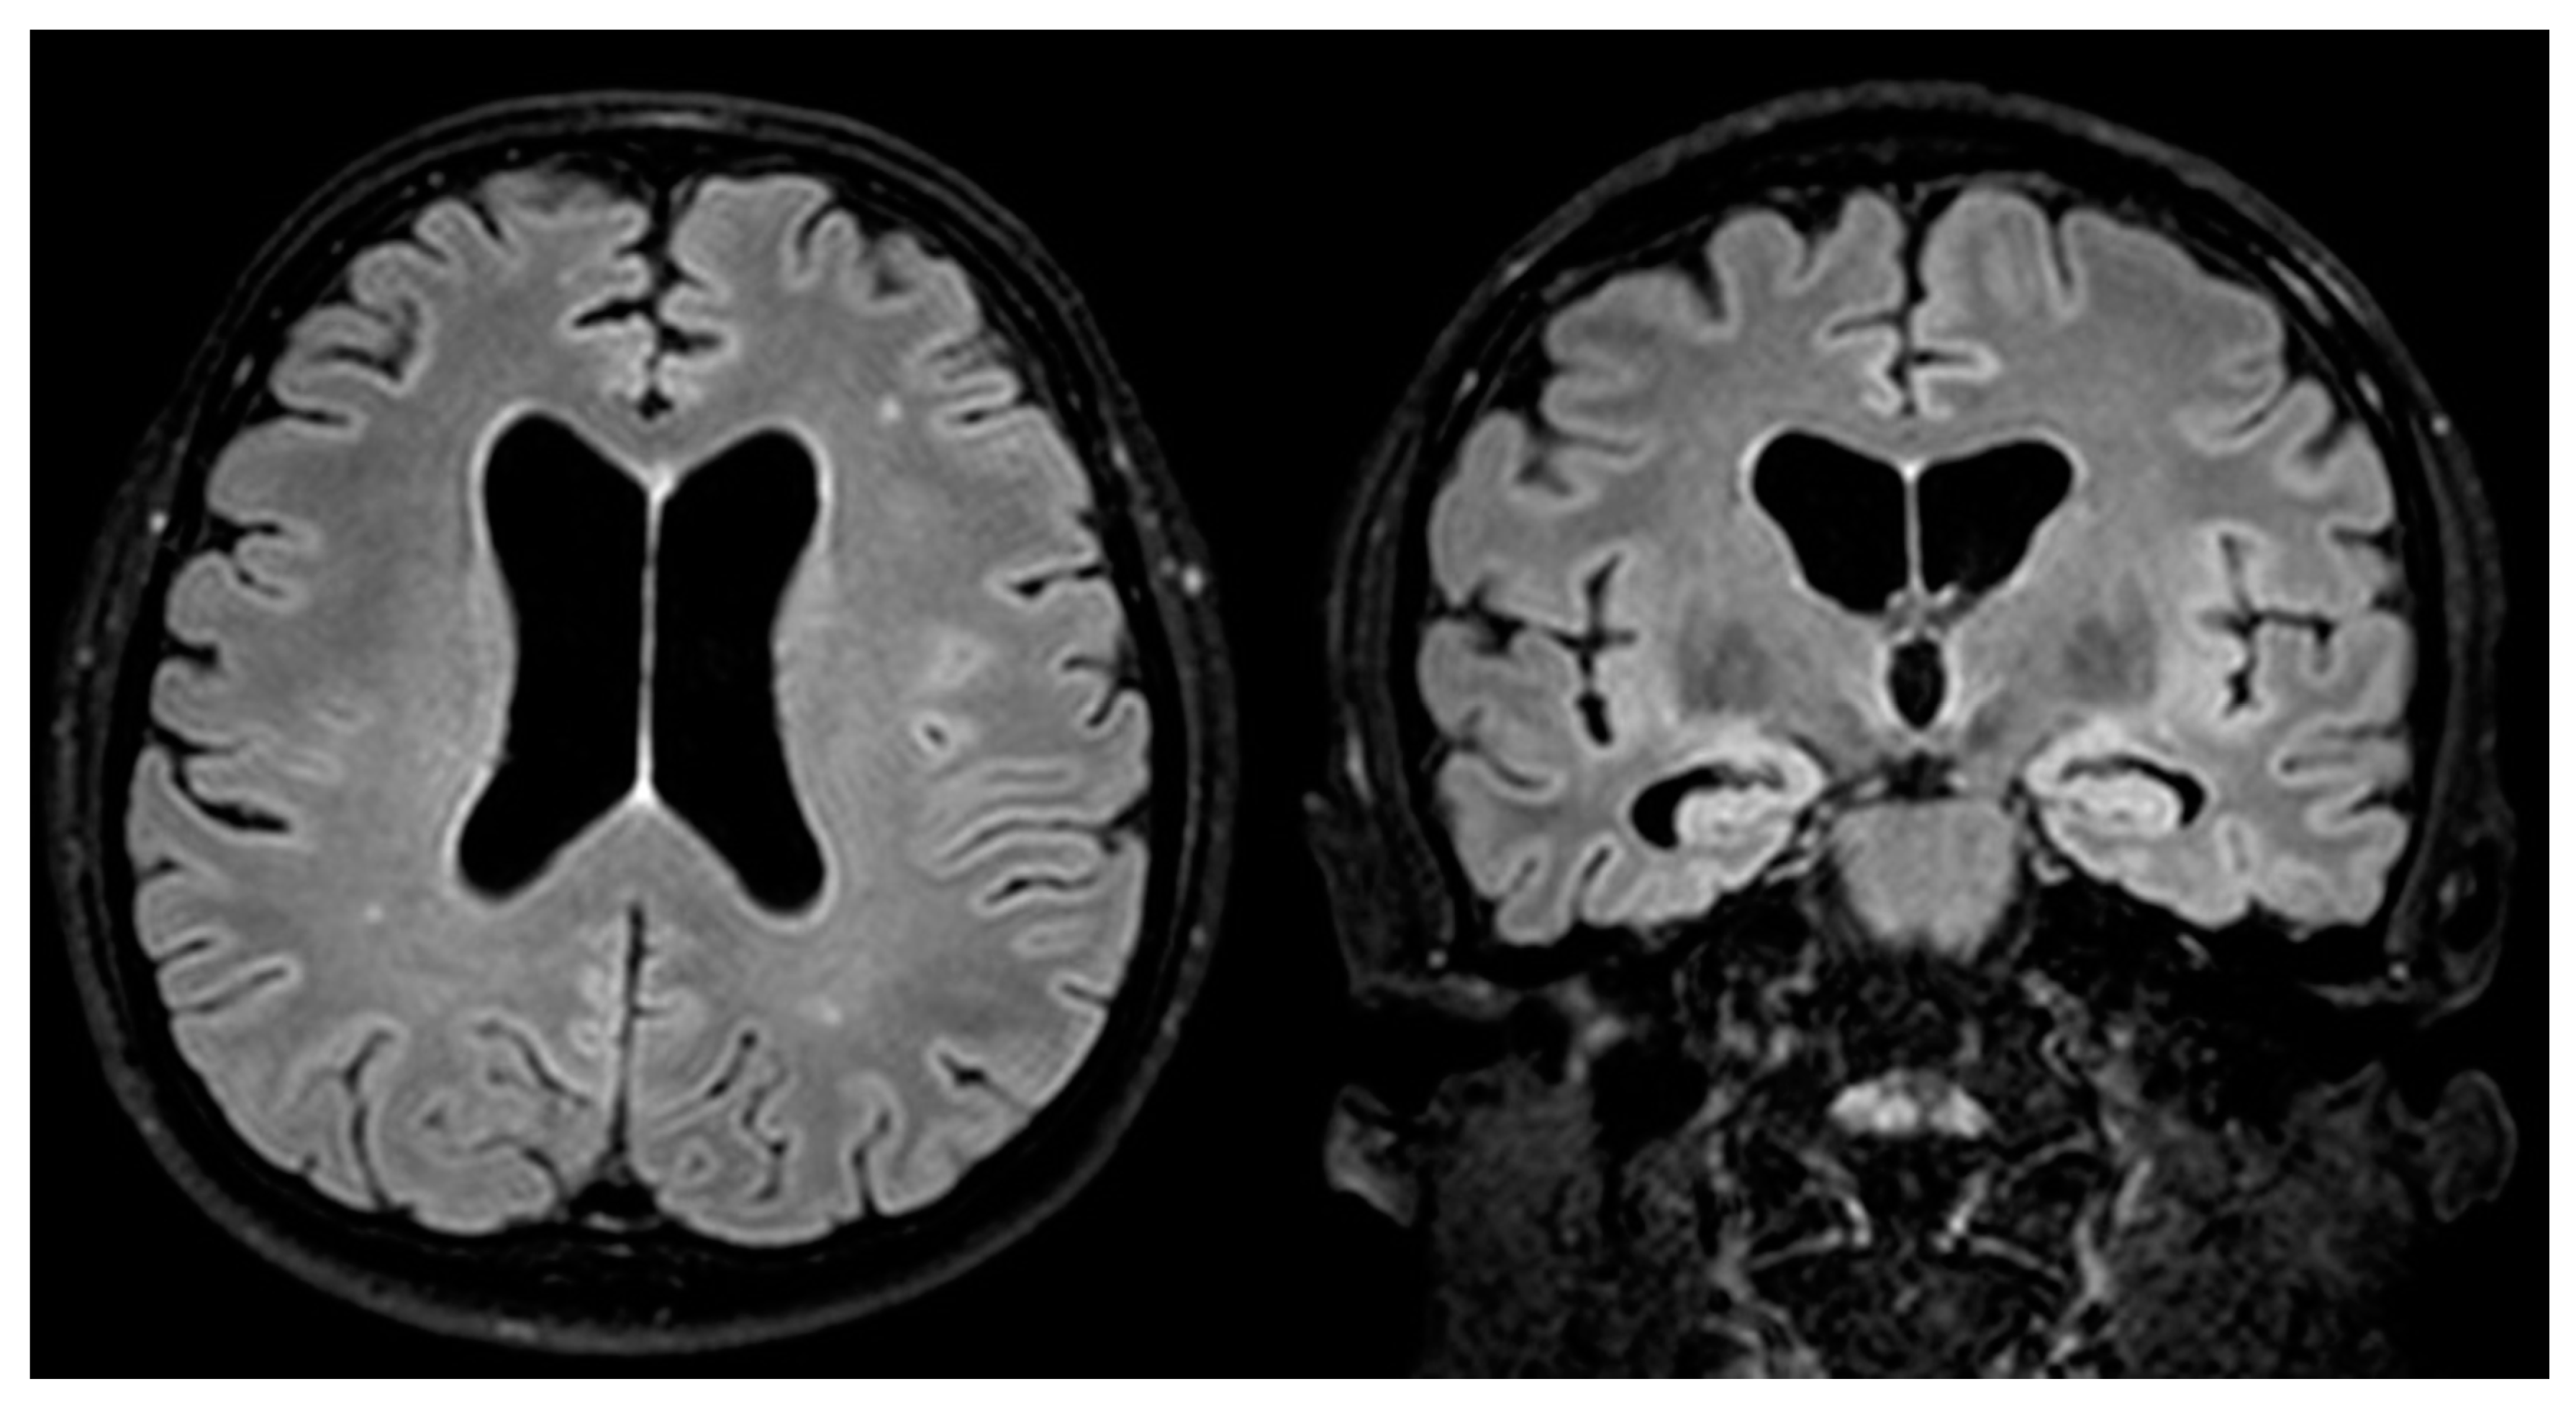

- Marano, E. Neurosyphilis with Complex Partial Status Epilepticus and Mesiotemporal MRI Abnormalities Mimicking Herpes Simplex Encephalitis. J. Neurol. Neurosurg. Psychiatry 2004, 75, 833. [Google Scholar] [CrossRef] [PubMed]

- Sesar, A.; Arias, M.; Requena, I.; Pereiro, I. Status Epilepticus Secondary to Luetic Encephalitis: Evolution of Neuroimaging Findings. J. Neurol. 2008, 255, 438–440. [Google Scholar] [CrossRef]

- Gaud, S.; Sauvée, M.; Muresan, M.; Gospodaru, N.; Foscolo, S.; Debouverie, M. Lésions Mésiotemporales Gauches et Amnésie Antérograde: Un Cas de Neurosyphilis. Rev. Neurol. 2011, 167, 833–836. [Google Scholar] [CrossRef] [PubMed]

- Derouich, I.; Messouak, O.; Belahsen, M.F. Syphilitic Limbic Encephalitis Revealed by Status Epilepticus. Case Rep. 2013, 2013, bcr2012008073. [Google Scholar] [CrossRef] [PubMed]

- Saunderson, R.B.; Chan, R.C. Mesiotemporal Changes on Magnetic Resonance Imaging in Neurosyphilis: Brief Communication. Intern. Med. J. 2012, 42, 1057–1063. [Google Scholar] [CrossRef]

| Atrophy | 9 (20%) | 3 (60%) | 0.08 | |

| White matter hyperintensities | 20 (44%) | 2 (40%) | 1.00 | |